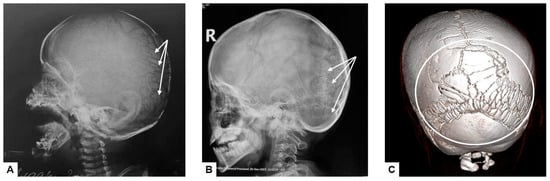

Figure 4. Abnormal ossification pattern of the skull vault: multiple wormian bones located in the region of lambdoid suture (white arrows on the lateral plane radiographs (A,B) and white circle on the reformed 3D CT image (C)).